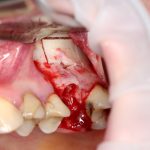

Простой синуслифтинг. Часть I.